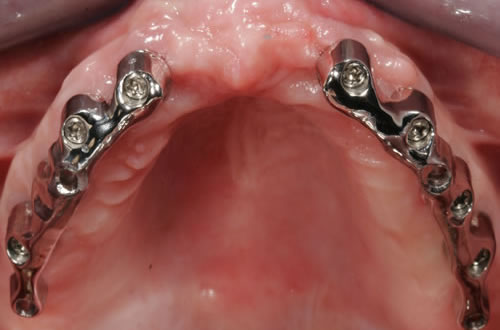

Für den zahnlosen Ober- und Unterkiefer werden dies häufiger Stegkonstruktionen oder Teleskopversorgungen sein (Abb. 8.8 bis 8.16).

Abb. 8.8: Individueller Steg auf 4 Implantaten im zahnlosen Unterkiefer.